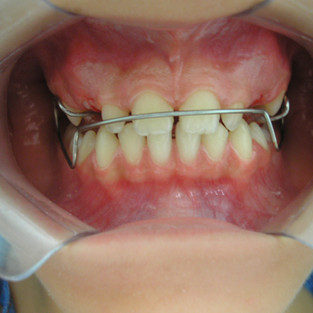

ANTES E DEPOIS DA CORREÇÃO DA CLASSE II- AVANÇO MANDIBULAR USANDO BIONATOR